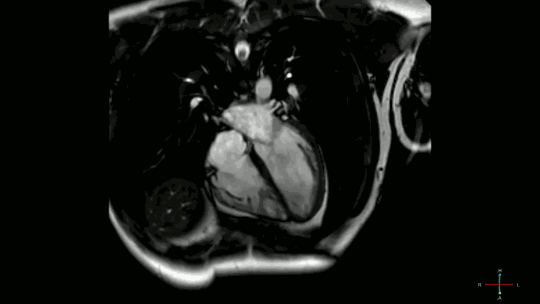

02核磁下的心脏跳动图